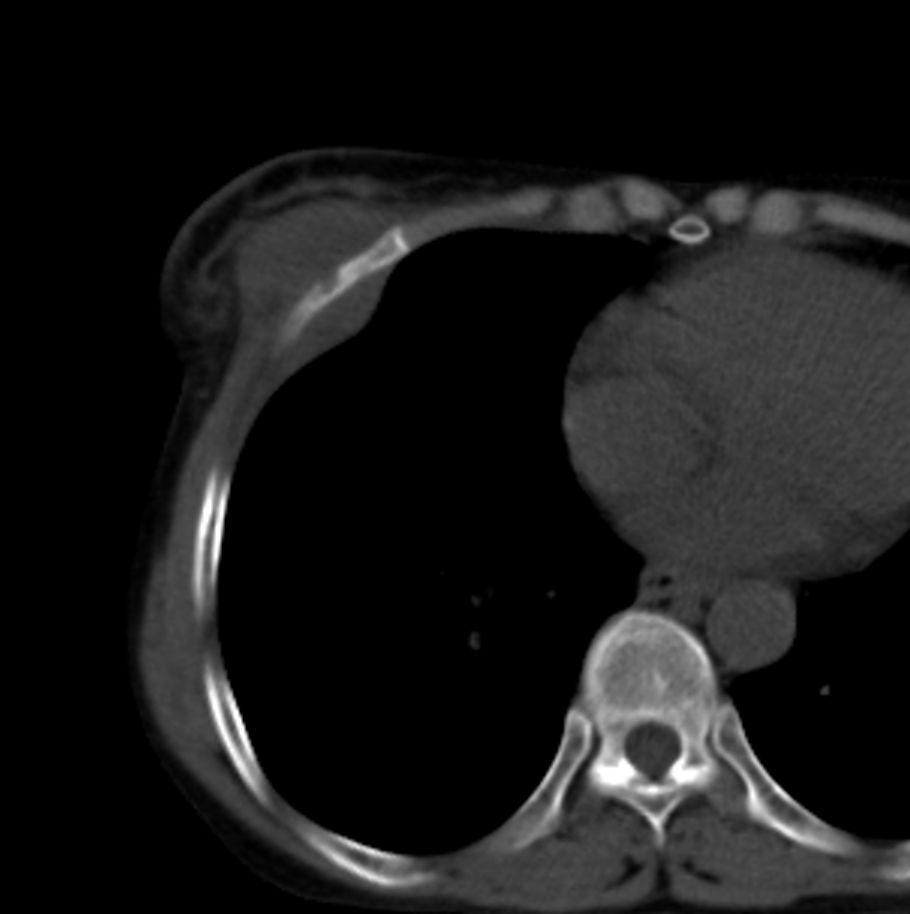

标题: CT21609:右乳包块1年,请各位讨论分析一下,乳腺CA, [打印本页]

标题: CT21609:右乳包块1年,请各位讨论分析一下,乳腺CA,

考虑---右乳癌并胸壁、肋骨、双肺转移。

考虑乳腺癌侵犯肋骨、胸壁及两肺转移可能性大。

右乳癌并胸壁、肋骨、双肺转移。

考虑右侧乳腺癌侵犯肋骨、胸壁及两肺转移。

支持考虑---右乳癌并胸壁、肋骨、双肺转移。

考虑右侧乳腺癌侵犯肋骨、胸壁及两肺转移可能。

考虑右侧乳癌并胸壁、肋骨及双肺多发性转移。

考虑右侧胸壁软组织肿瘤,肉瘤可能性大,双肺转移